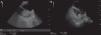

During an endobronchial ultrasound procedure, a round hyperechoic image was seen in the left atrial appendage, along with an enlarged atrial diameter (Fig. 1A and B). Atrial thrombus was suspected, so the cardiologist was contacted, who confirmed the diagnosis by transesophageal echocardiography. The procedure was suspended, and it was confirmed that the patient was not taking his prescribed anticoagulation, and treatment with low molecular weight heparin began.